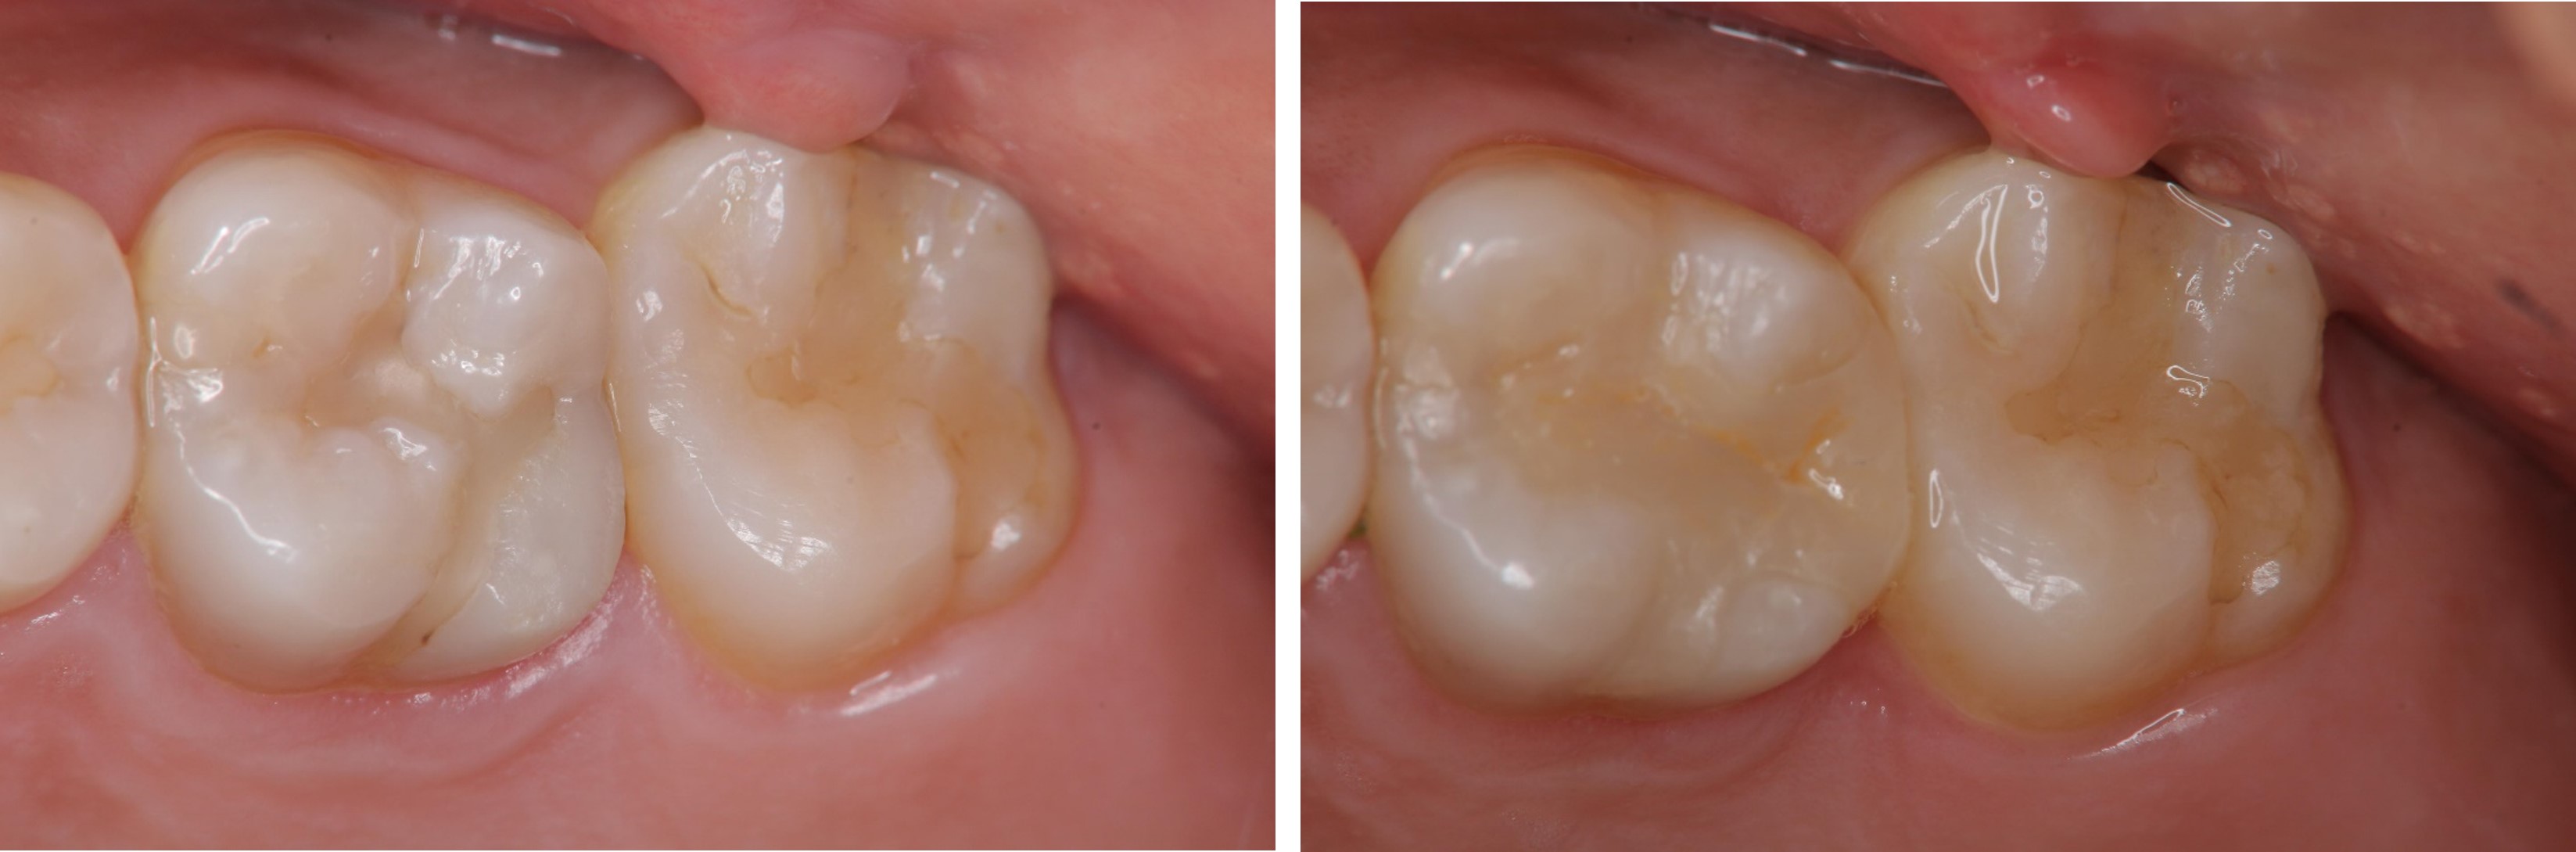

術前、術後比較